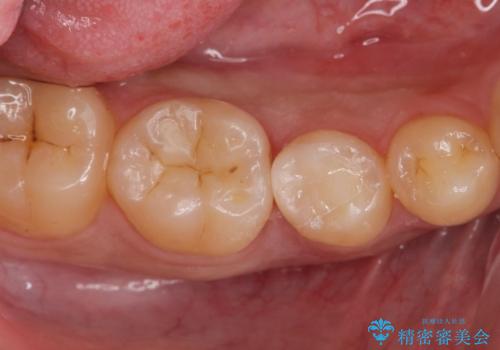

- 昔他院で虫歯治療をしたところが虫歯が再発したとのことで来院。

古い材料(プラスチックの樹脂)をとり、拡大鏡下で虫歯を全て取り除き、

ゴールドインレーにて治療しました。

歯の外側の面が少し欠けていて、そこの部分を覆う(ゴールドの範囲が広くなる)か

そこの欠けてる部分は虫歯ではないので削らないで、最小限にして詰め物を作るか相談したところ

欠けているところは何十年も昔から欠けていて特に何もない。なるべく歯を削りたくないとの事だったので

最小限で詰め物の治療をしました。

インレーについて

ゴールドの詰め物は歯質との隙間ができにくく

虫歯の再発リスクが少なくなります。